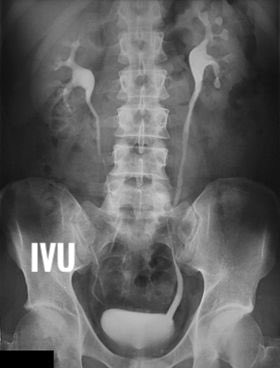

Definition : its a radiographic examination by contrast media to image the kidney - ureter - urinary bladder.

I.V.U = intravenous urography

I.V.P = Intravenous pyelography

منتقل الان لفحص الكلى : الفحص يكون على مراحل ولكل مرحله وقت معين وتقسيمها كالاتي :

- nephtogram phase ( 5min )

- compression bad phase ( 10 to 15 min )

-release phase ( 25 min )

- post micturition